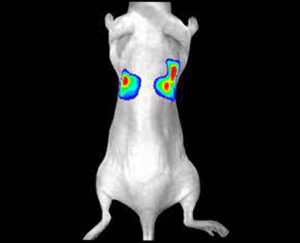

Image analysis is a critical component of clinical and preclinical imaging research, providing a means of quantifying and interpreting the data generated by imaging modalities such as PET, SPECT, and CT. In clinical imaging, image analysis is used to aid in diagnosis and treatment planning. For example, in oncology, image analysis can be used to assess the response to chemotherapy and radiation therapy, providing a means of monitoring the effectiveness of treatment and making adjustments as necessary.

In cardiology, image analysis can be used to evaluate blood flow and cardiac function, enabling the diagnosis and treatment of heart disease. In preclinical imaging research, image analysis plays a crucial role in the development of new treatments and therapies. Image analysis algorithms can be used to quantify the effects of drug treatments or surgical procedures on biological processes such as blood flow and metabolic activity. By providing a means of objectively assessing treatment efficacy, image analysis helps to optimize treatment protocols and improve patient outcomes.

The same image analysis techniques can be applied to both clinical and preclinical images, allowing for a seamless transition between research modalities. Moreover, image analysis has additional applications in clinical research, beyond the evaluation of disease progression or response to therapy. For example, image analysis can be used for radiation treatment planning to optimize the radiation dose and minimize side effects.

At our company, we provide a wide range of image analysis services for both preclinical and clinical imaging research. Our team of experts has extensive experience in conducting image analysis for various modalities, including PET, SPECT, CT, and optical imaging. We offer a comprehensive set of services, such as image registration, segmentation, quantification, and statistical analysis. We understand the importance of accurate and precise image analysis in the success of research projects, and we use state-of-the-art software and techniques to deliver reliable and reproducible results.